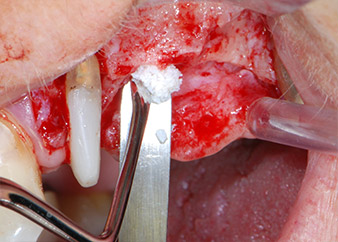

Prior to implant placement, infected tissue was removed from the alveolar bone in the implant site and around the abutment teeth with an insert originally designed for bone shaping and collecting bone chips (Piezomed, insert B5) (Figs. 6 and 7).

Prior to implant placement, and following verification of an intact Schneiderian membrane (Fig. 9), the internal sinus floor was augmented at both implant sites by means of xenogeneic bone substitute material (Bio-Oss, Geistlich Biomaterials) (Fig. 10).